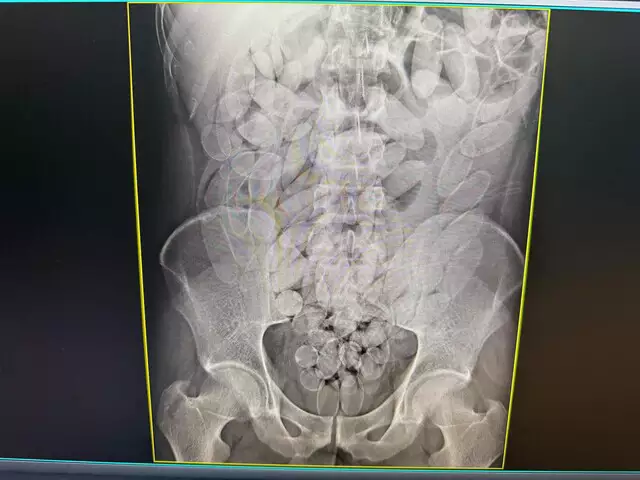

Segundo ele, “a Angiotomografia Coronária é um exame de imagem não invasivo, utilizado para avaliar a presença de placas de gordura nas artérias coronárias, possibilitando o diagnóstico precoce de doenças cardíacas e a prevenção de eventos graves, como infarto do miocárdio. Trata-se de um exame de alta precisão e relevância clínica, que contribui significativamente para o acompanhamento de pacientes com histórico familiar de doenças cardíacas, hipertensão, diabetes, colesterol elevado ou outros fatores de risco cardiovascular”.

O parlamentar reforçou que “atualmente, esse exame possui custo elevado na rede privada devido à tecnologia avançada necessária, o que torna seu acesso limitado para a população de menor poder aquisitivo. A inclusão da Angiotomografia Coronária na rede pública de saúde de Ponta Porã representaria um importante avanço na política de prevenção e cuidado à saúde cardiovascular, ampliando o diagnóstico precoce e reduzindo custos com tratamentos de alta complexidade no futuro”.